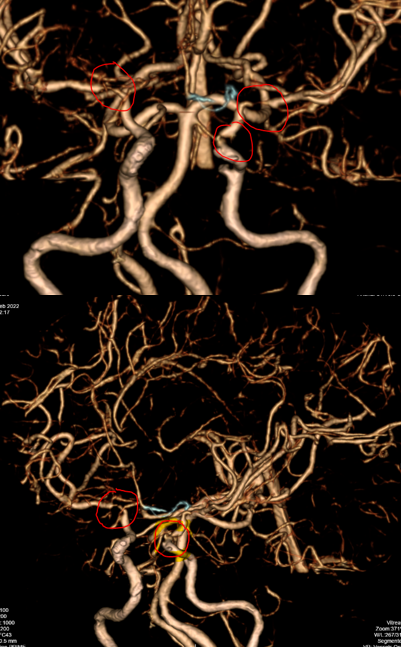

Bệnh nhân tiếp tục được được chụp CLVT mạch máu não: Phát hiện hẹp khít động mạch cảnh trong trái đoạn mấu giường và động mạch não giữa đoạn M1 hai bên.

Một bệnh nhân trẻ tuổi, CLVT mạch máu não nghĩ nhiều đến hình ảnh của bệnh Moya Moya, vì vậy bệnh nhân được chỉ định chụp DSA mạch não để khẳng định chẩn đoán đồng thời tiên lượng khả năng điều trị bệnh.

Hình chụp DSA động mạch cảnh trong phải và trái: hẹp khít động mạch não giữa hai bên đoạn M1.

Hình chụp DSA động mạch cảnh trong trái: hẹp khít động mạch cảnh trong trái đoạn mấu giường.

Hình chụp DSA động mạch đốt sống: bàng hệ cho hệ tuần hoàn trước từ hệ thống tuần hoàn sau

Bệnh Moya Moya là bệnh lý mạch máu hẹp tại gốc một số động mạch lớn trong sọ thuộc tuần hoàn trước (thuộc động mạch cảnh trong). Quá trình hẹp dần dần nên cơ thể thích nghi bằng các tuần hoàn bàng hệ bù cho vùng thiếu hụt tuần hoàn. Tuần hoàn bàng hệ phát triển tại chỗ hẹp bằng rất nhiều mạch máu nhỏ và yếu, dễ hình thành các phình mạch nhỏ và vỡ gây chảy máu não. Nếu tuần hoàn bàng hệ một lúc nào đó không đủ cấp máu cho não sẽ gây nên nhồi máu não tái đi tái lại. Trên chụp mạch, các mạch nhỏ tại chỗ hẹp tạo nên hình “những làn khói tỏa” (puff of smoke). Bệnh lấy tên một bác sĩ người Nhật là người đầu tiên mô tả về bệnh này trong y văn.